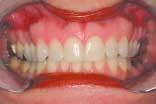

The assistant retracts the lips for the next set of images. These two images are the arches in occlusion and slightly open. The image of the teeth in occlusion gives us information on overbite, overjet, cross bites, gingival recession, Golden Proportion, Shimbashi number, and exostosis. A periodontal probe can be placed on the central incisor as a reference for measurement. This view can be used to analyze and diagnose Golden Proportion on a printed view with a ruler and pen or with measurement tools found in many software applications.